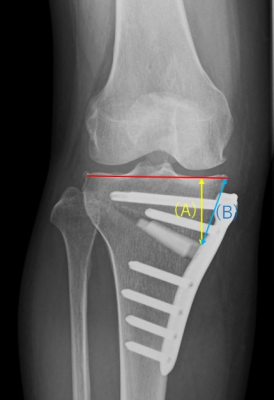

内側開大式高位脛骨骨切り術(OW-HTO)では、MCL浅層の解離が必須です。MCL解離直後は内側が緩むが、骨切り部開大後は術前と同等になるとの報告がある一方、内側がややタイトになるという報告もあり、術前後における内側laxityの変化を定量的に検討した報告は限られていました。本研究では、OW-HTO前後における内側laxityの変化について定量的に検証し、その影響因子や臨床成績との関連などを調査しました。術前とOW-HTO後1年時の外反ストレス(15㎏)膝正面XpにおけるJLCAや関節裂隙幅などを計測しました。結果は、12例/40例(30%)において、内側関節裂隙の開大を伴う1度以上のJLCAの変化(内側の緩み)を術後に認めました(図A)。術前後の内側laxityの変化(ΔJLCA)に有意に相関を認めた因子は、骨切り高位(Distance AとB)であり、ΔJLCA > 1°のカットオフ値はDistance Aで35mm、Distance Bで39mmであった。一方、ΔJLCAは術後1年のKOOSとの有意な関連は認めず、臨床的意義に関しては今後の課題です。関節面に近い骨切りでは、MCLの解離もより近位となることが術後の内側の緩みの原因となったかもしれないと結論付けました(Soejima Y, Akasaki Y, et al. KSSTA 2021)。

図B